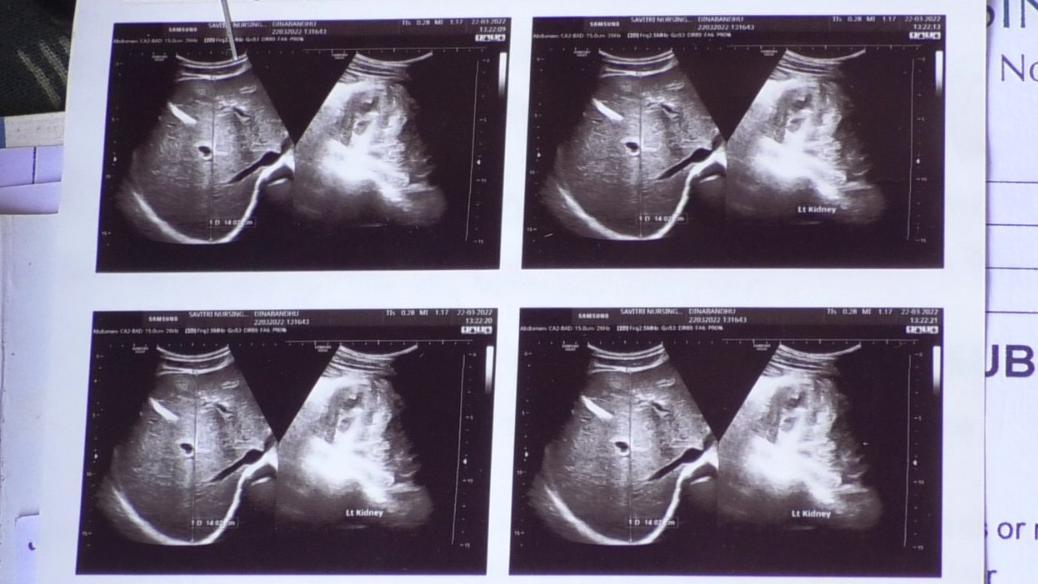

“సాధారణంగా రక్తంలో సిరం క్రియాటినిన్ 1.2 mg/dL (మిల్లీ గ్రామ్/డెసీలీటర్ - వీటిని స్థానికులు పాయింట్లు అంటారు) కంటే ఎక్కువగా ఉంటే, మూత్రపిండాలు సరిగా పని చేయడం లేదని అర్థం.

ఉద్దానం ప్రాంతంలో దాదాపు 15 వేల మందికి సీరం క్రియాటినిన్ 3 నుంచి 25 mg/dL ఉంది. 80 శాతం కంటే ఎక్కువ కిడ్నీలు పని చేయడం మానేస్తే, వారికి డయాలసిస్ అవసరమవుతుంది” అని శ్రీకాకుళానికి చెందిన నెప్రాలజిస్ట్, కిడ్నీ వ్యాధిగ్రస్థుల కోసం నిర్వహిస్తున్న సామాజిక ఆసుపత్రి వైద్యులు డాక్టర్ విద్యాసాగర్ బీబీసీకి తెలిపారు.

“5 పాయింట్లు ఉంటే కిడ్నీ వ్యాధి బాధిత పెన్షన్ ఇస్తామని అన్నారు. కిడ్నీ వ్యాధి వచ్చి రెండు సంవత్సరాలు అవుతుంది. 6 పాయింట్లు దాటిపోయింది. కానీ పెన్షన్ నాకు రాలేదు” అని సహలాల పుట్టుగ గ్రామానికి చెందిన కిడ్నీ వ్యాధి బాధితుడొకరు బీబీసీతో చెప్పారు.

“పెన్షన్ అందాలంటే కేవలం పాయింట్లే కాదు, కిడ్నీ శుద్ధి సామర్థ్యం, కిడ్నీ పరిమాణం, కిడ్నీ పని చేయని శాతం, క్రియాటినిన్ స్థాయి 3 నెలల వ్యవధిలో రెండు సార్లు వైద్య పరీక్షల్లో 5 కంటే ఎక్కువగా ఉన్నట్లు నిర్ధారణ కావడం వంటి లెక్కలు ఈ ఆర్థిక సాయం పొందే అర్హతను నిర్ణయిస్తాయి” అని జిల్లా వైద్య, ఆరోగ్యశాఖ అధికారి బీ. మీనాక్షి తెలిపారు.